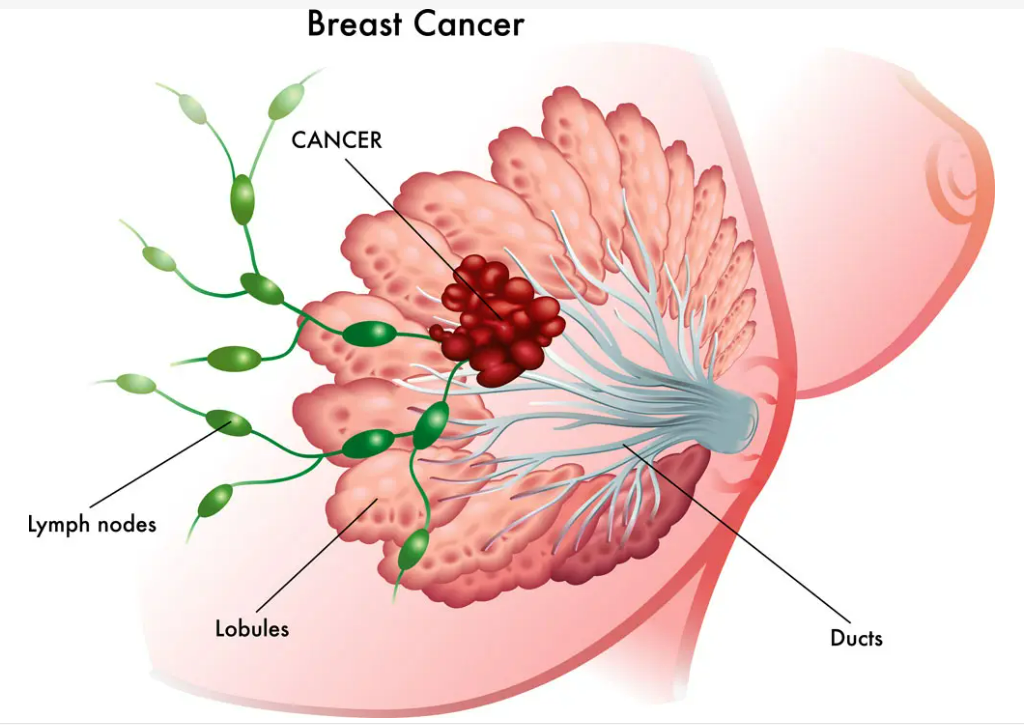

乳腺癌的疾病分型多种多样,其中三阴性乳腺癌因预后极差被称为“乳腺癌之王”。整体乳腺癌的生存情况较其他癌症要好,但晚期三阴性乳腺癌的5年生存率仅为11%。很少有三阴性乳腺癌(TNBC)患者受益于免疫检查点抑制剂,完全和持久的缓解非常罕见。